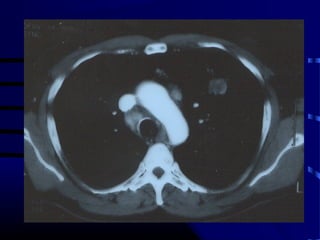

Question

• Patient is a 65 year old smoker with

following CXR and CT scan of chest:

• What test do we order next?

• A. CT-guided lung biopsy.

• B. Video Assisted Thoracic Surgical open

lung biopsy with possible lobectomy.

• C. PET scan.

• D. PFT’s.

• E. CT scan of head.